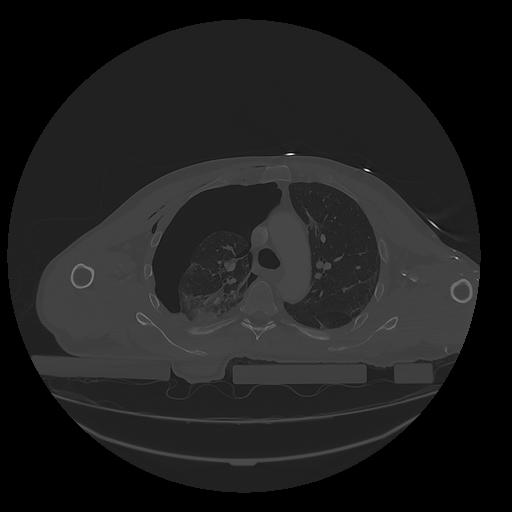

31 PULMON,CE,Vol,1.0,PULMON,,